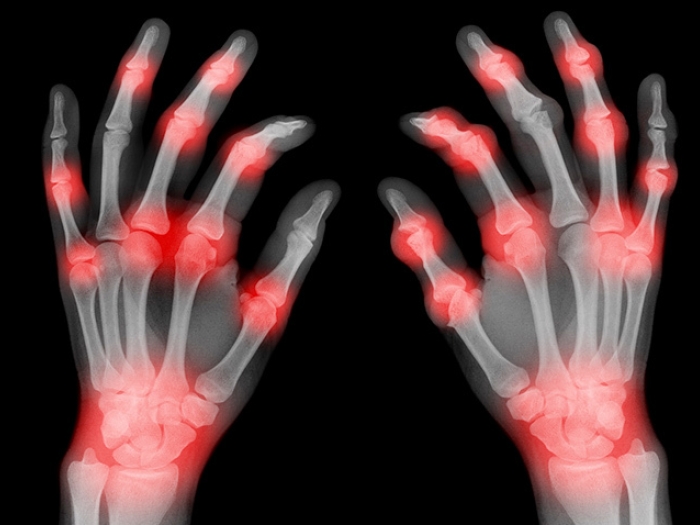

Featured News & Stories hands of xray finfers with red spots

Health Lab

How to live pain-free with arthritis

Arthritis of the hands, wrist and fingers can be unbearable, but a doctor says you don’t have to live in agony.